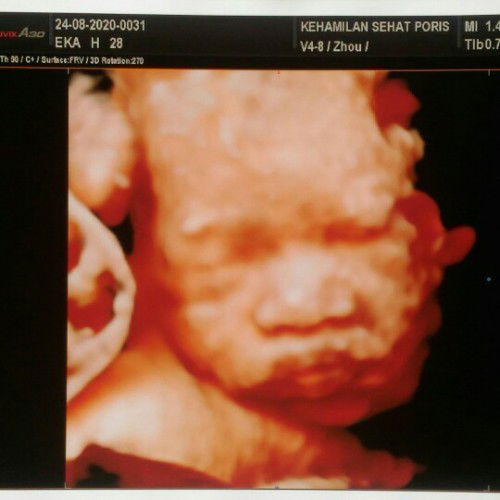

Baby Girl

Assalamualaikum bunda.. ini baby girl ku.. dy lg manyun krn bt nunguuin om dokternya kelamaan hehe.. usg minggu kemarin pas uk 28 week.. hpl 20 november 2020 doain yaa supaya aq & baby ku sehat terus & dilancarkan kehamilan sampai persalinan nanti.. btw bunda" disini yg hpl nya udh deket gimana persiapannya ?